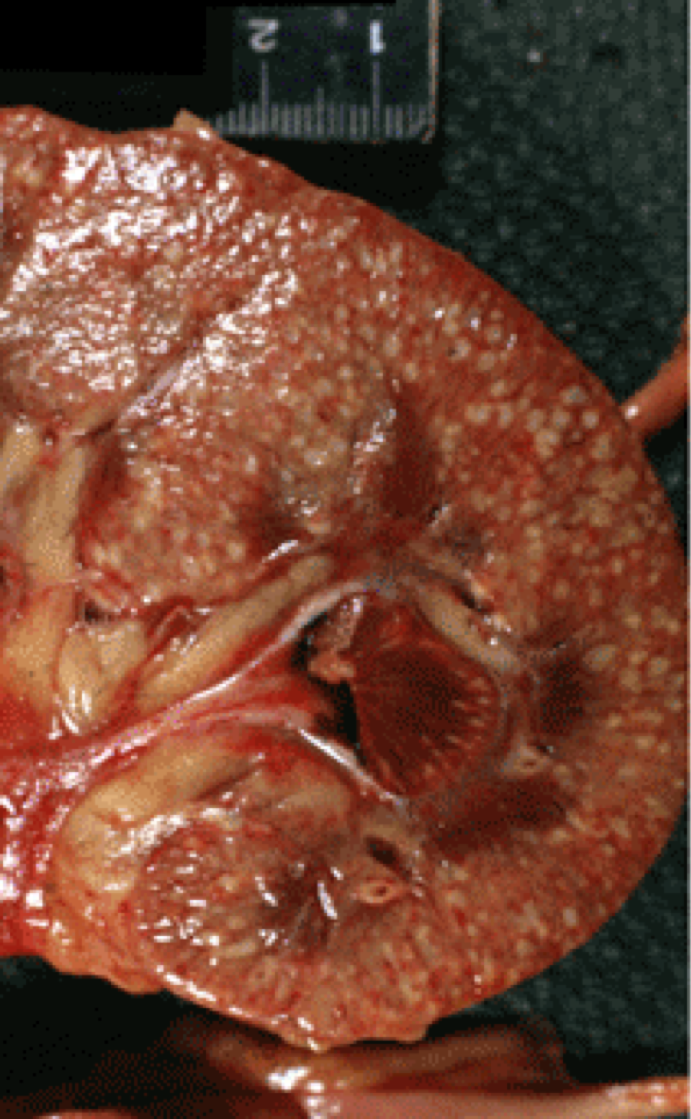

Normal kidney on the left. What is wrong with the left?

Scars. Could be from pyelonephritis, infarct, etc. Need biopsy